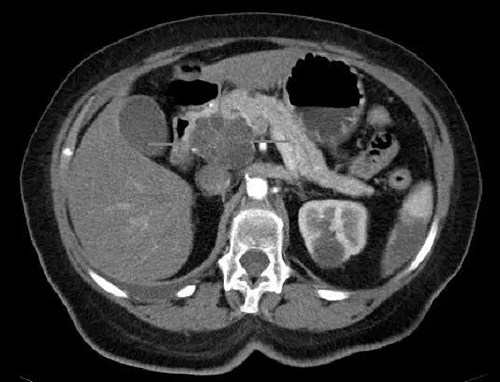

胰头癌和囊腺癌具有iv对比度的轴向CT图像(图片来源:Science)